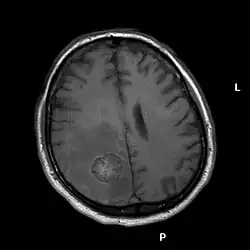

Radiochirurgie

EvG-Färbung. Vergrößerung 1:200

Unter Radiochirurgie versteht man die Anwendung einer hohen Strahleneinzeldosis, die perkutan (durch die Haut) und stereotaktisch appliziert wird. Sie kann bis zu einem Metastasendurchmesser von drei Zentimetern eine Alternative zur konventionellen Operation darstellen und wird auch bei Patienten, die aufgrund eines schlechten Allgemeinzustands oder der Lokalisation der Metastase (beispielsweise im Hirnstamm) nicht operabel sind, eingesetzt. Je nach Größe der behandelten Metastase werden Dosen zwischen 15 und 24 Gray toleriert.